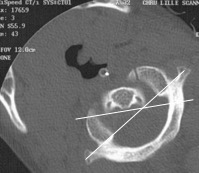

les facettes articulaires sont pratiquement horizontales à la naisance, elles deviennent progressivement plus obliques ; les condyles deviennent plus coaptés dans les facettes supérieures de C1 (Cf. ci-contre)